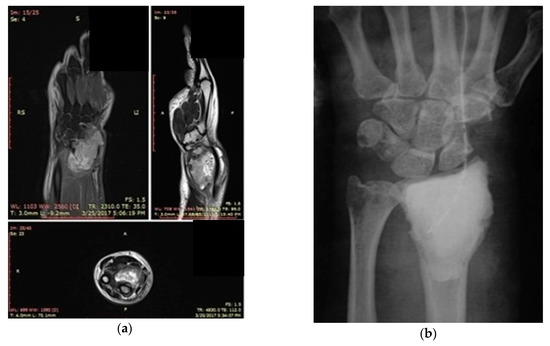

3.1. Case 1